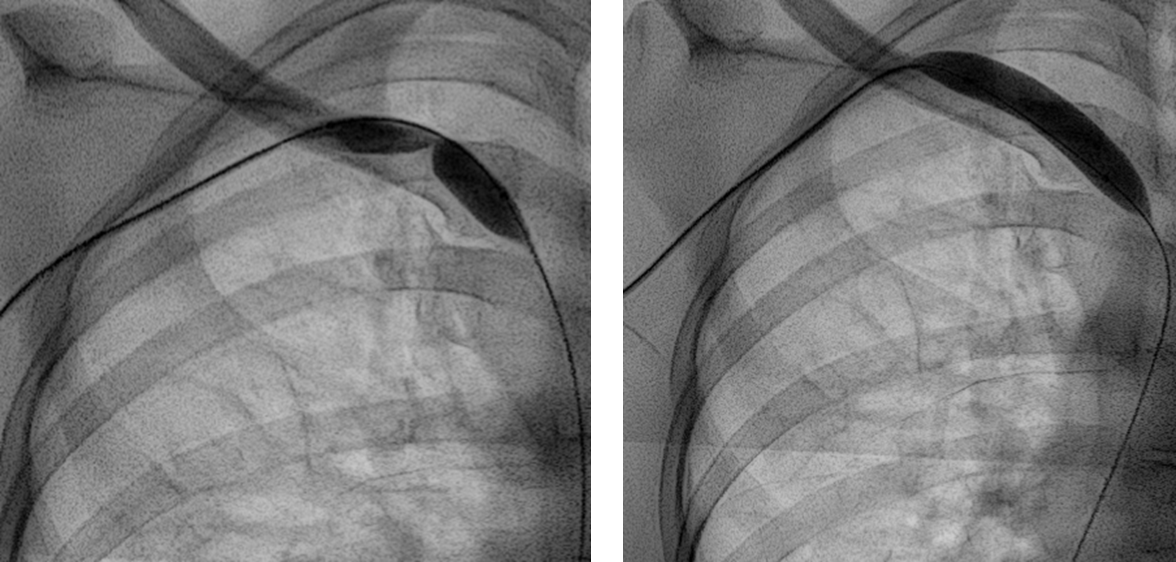

인터벤션 치료로는 경피적 혈관성형술, 혈관내 스텐트설치술, 혈전용해술이 있습니다.

이 중 경피적 혈관성형술을 가장 자주 시행하므로 이에 대해 말씀드리겠습니다.

경피적 혈관성형술이란 피부를 미세 절개한 뒤, 직접 혈관으로 접근해서 좁아진 혈관을 확장해주는 시술입니다.